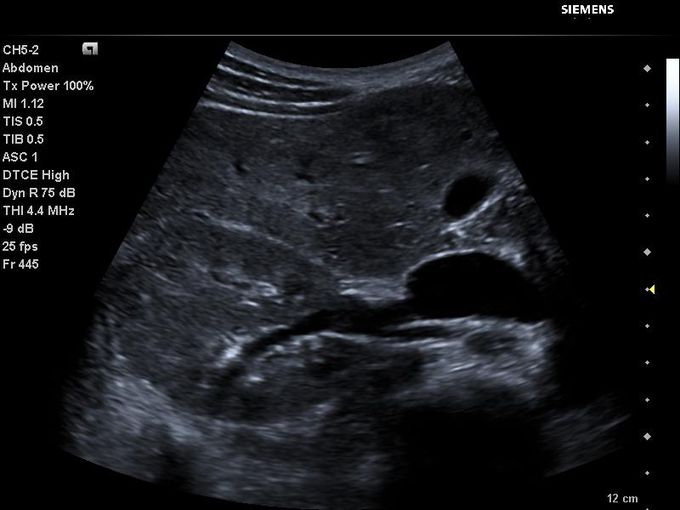

Кроме новой техники, можно заказать восстановленные медицинские системы: ультразвуковые сканеры, томографы, флюороскопы, ангиографы и хирургические установки С-дуга.